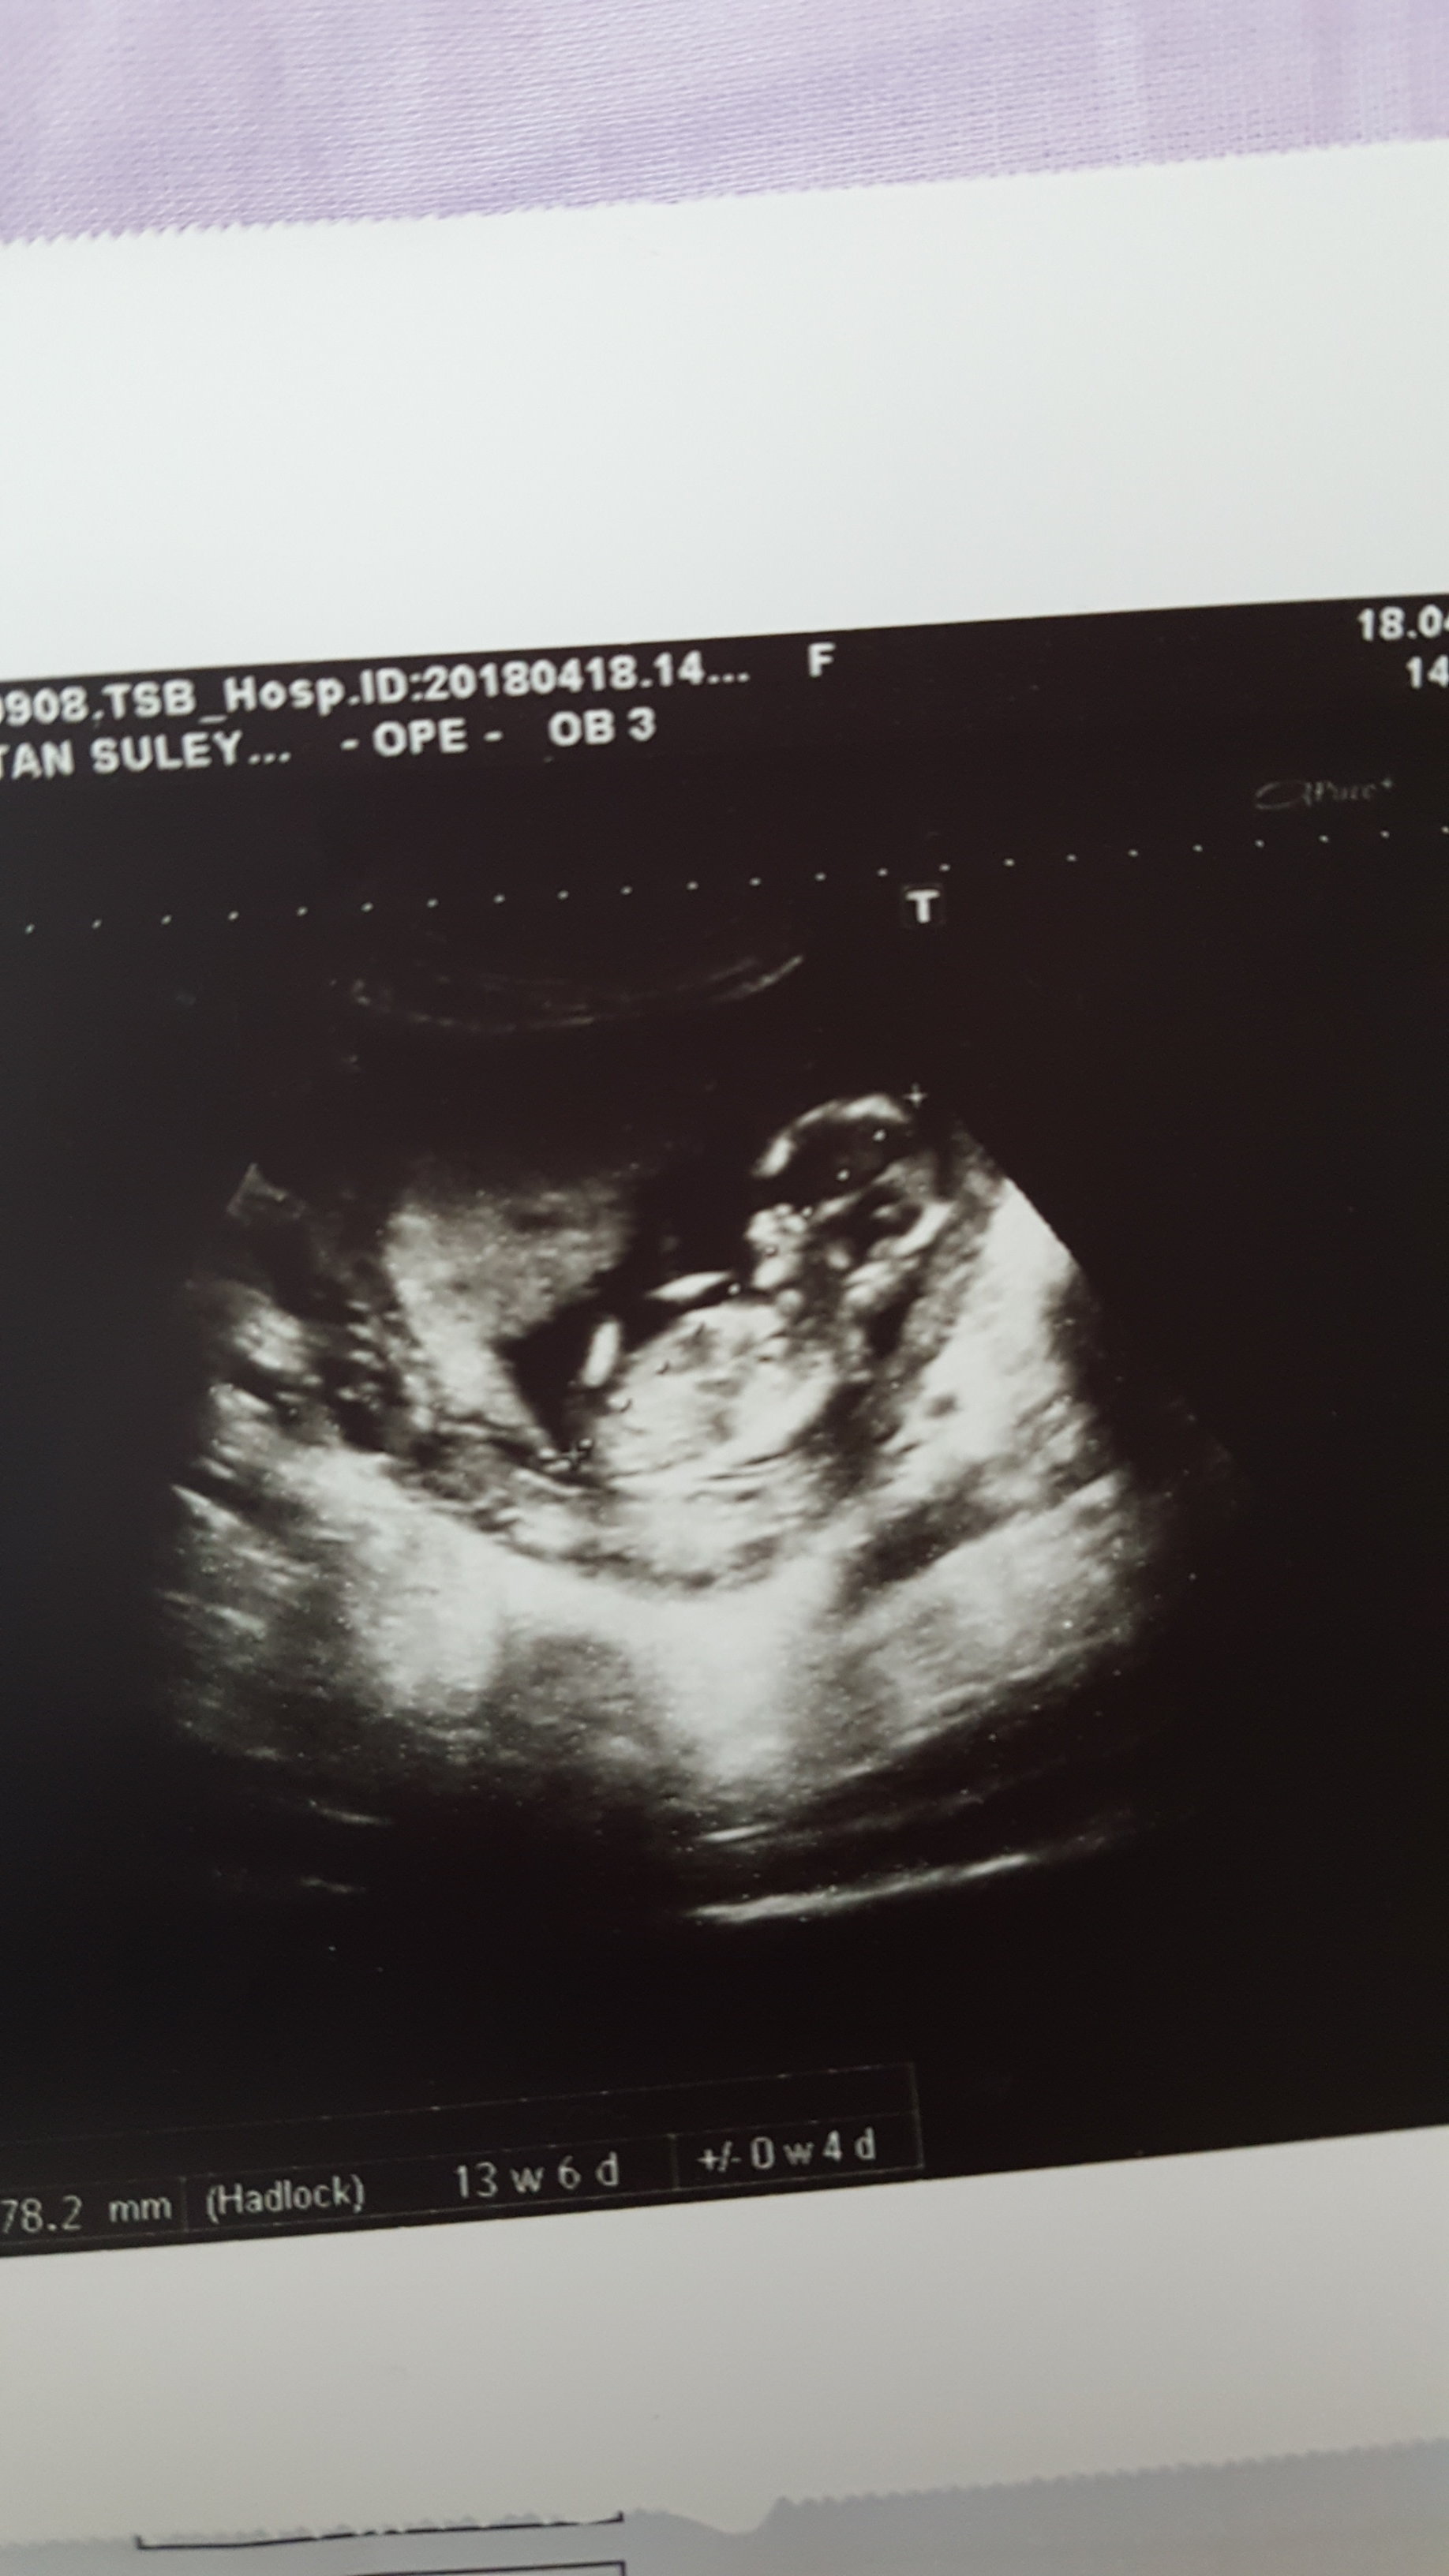

Bebeğin cinsiyetini belirme de , son günler de ilginç bir yöntem konuşuluyor. Nub teorisi . Bu teori nin % 88 cinsiyeti belirlediği iddia ediliyor. Gebeliğin 12- ve 14 . haftasın da bu teori ile bebeğin cinsiyetini öğrenmek mümkün. Yapılan çalışmalar , 12. hafta da %88 -90 doğruluk üzerine kanıtlanmıştır.Bu iddia hekimler tarafın dan ortaya atılmaktadır.İddia desekte sevgili anne adayları bu metodun doğruluk payı varmış..

Daha önce de belirtildiği gibi, hem erkek hem de kız fetusların gelişme aşamalarında genital bir tüberkül vardır. Bu genital tüberkül bir nub olarak adlandırılır.Nub Teorisini kullanarak bebeğinizin cinsiyetini belirlemek, büyük oranda ultrason resmine bağlıdır. Bu, nub resminin sonucu belirlemeniz için mükemmel olması gerektiği anlamına gelir.

10 haftalık gebeliğin başlamasından önce, genital yumrunun hem erkek hem de kız fetüslerinde aynı olduğu görülüyor . 11 hafta, görünürlük mükemmel koşullardaysa, tahmin etmek mümkün olabilir, ancak doğruluk 12-14 hafta kadar büyük olmayacaktır. 14 hafta sonra, sonograf uzmanının randevuda cinsiyet belirlemesi mümkün olabilir.

Resimde gördüğünüz gibi üst taraftaki çıkıntı paralel ise bebek kız, 30° lik açıyla yukarı bakıyorsa bebek erkektir.

Gebeliğin 9. haftası fetusun bacaklarının arasın da küçük bir çıkıntı görülür. Gebeliğin 12. ve 14 haftası bu topak çıkıntı nın açısı değerlendirilerek , cinsiyet tahmini yapılır. Çıkıntı kızlar da 30 derecenin altın da ve düzdür erkekler de ise 30 derecelik açıdan büyüktür.

Özet ; 11-13 haftalar arasında, tüm bebekler genital tüberkül denilen kendi bacaklarının arasına bir topak var ve bu teoriye göre topak açısı bir olup olmadığını gösterecektir Kız veya erkek olduğu bu açılara göre değerlendirilerek söylenir.Bu arada bilimsel verilere dayarak şunu da belirtelim.Ultrason ile bebeğin cinsiyeti en erken 3. ay bittiğinde yani 13 hafta civarında anlaşılıyor. Bazı durumlar da bebeğin cinsiyeti bu haftalar da görülmeyebilir. 16-17 haftalarda daha net izlenir. 20. haftaya yaklaştıkça cinsiyet en net şekilde değerlendirilir.

Merhaba, ultrason görüntünüzün kalitesi iyi değil. Nub çıkıntısı belirsiz .Emin olmamakla birlikte bebeğinizin cinsiyetinin kız olduğu kanısındayım. Hatırlatma fayda var bebeğinizin cinsiyetini net olarak 17-19-20. haftalarda öğrenebilirsiniz.